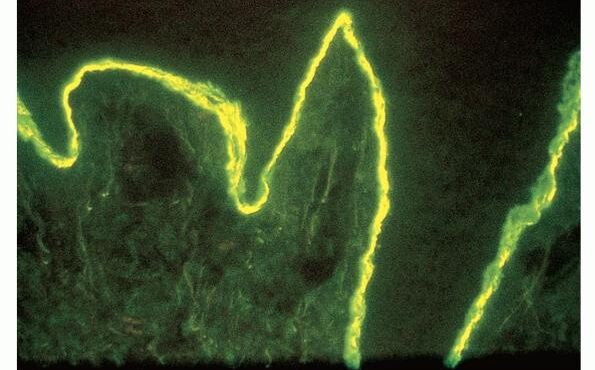

Epidermolysis bullosa acquisita = انحلال البشرة الفقاعي المكتسب Epidermolysis Bullosa Acquisita Classically, EBA is a noninherited disorder of acquired skin fragility. This presentation of EBA was the only one recognized until later. Blisters develop on noninflammatory bases with a predilection for acral areas. Scarring and milia formation ensue. A characteristic nail dystrophy and alopecia are […]